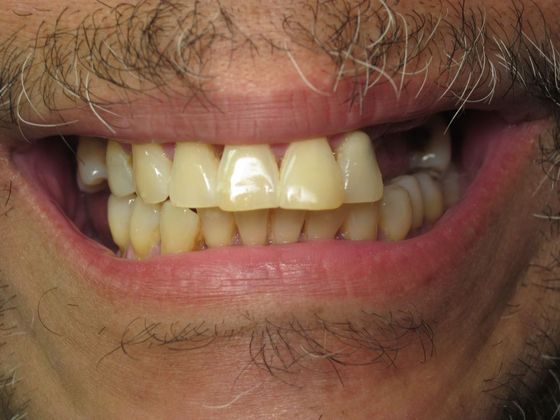

Individual Implants: Case 6

Description

As a night shift worker Roy, had very little time to deal with his smile and dental work. He finally could no longer deal with his half smile and came in for help. With just a few visits, accommodated to his schedule, he is now smiling fully again, from ear to ear!